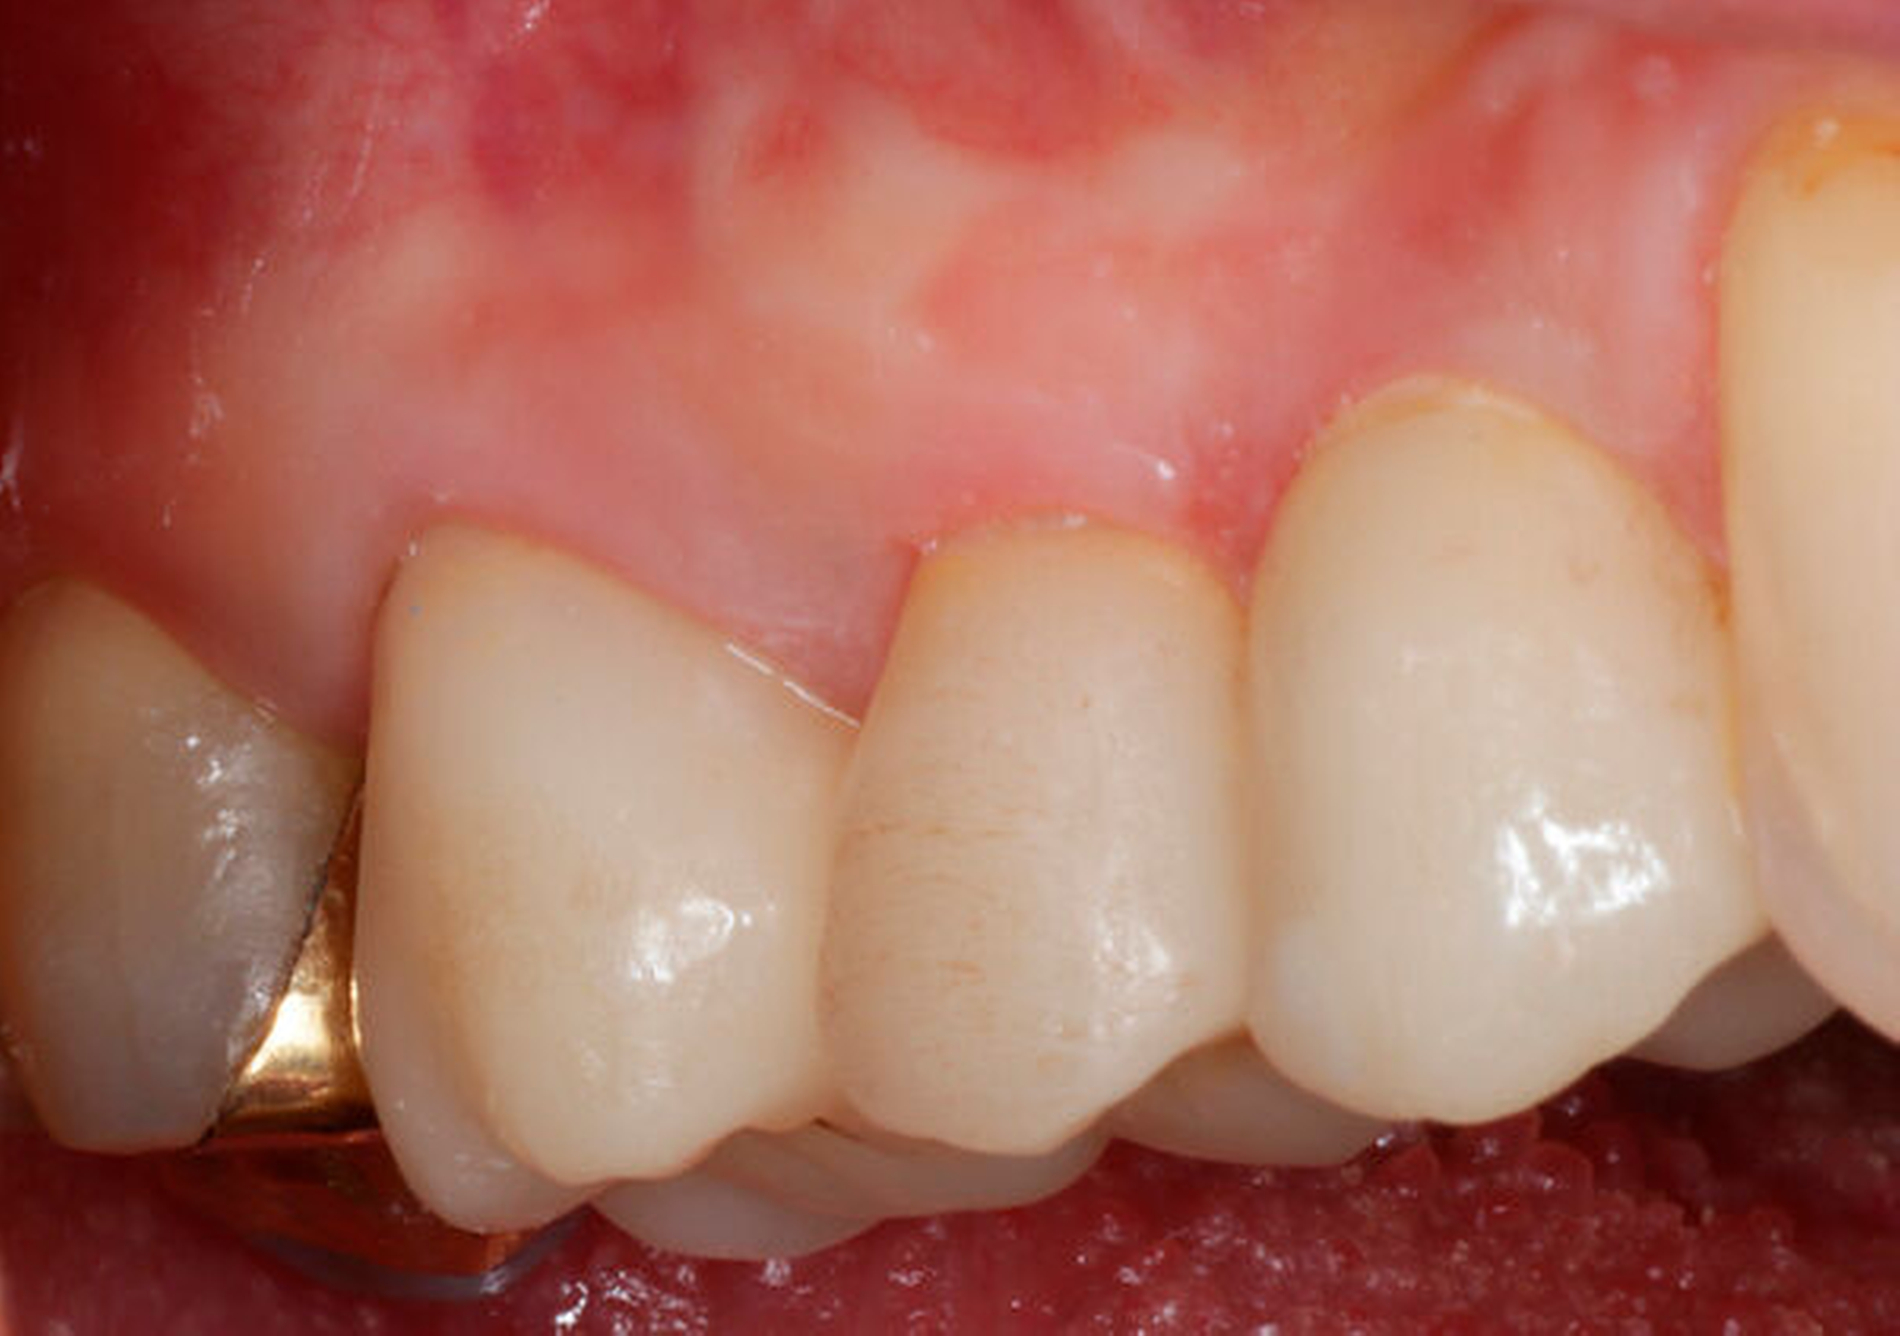

Eine 54-jährige Patientin stellte sich 2018 in der Praxis vor, nachdem sie beim Essen ein Goldinlay an Zahn 16 verloren hatte. Sie klagte über eine Aufbissempfindlichkeit des Zahnes sowie über das Gefühl einer Lockerung. Klinisch zeigte sich eine tiefe Fraktur des Zahnes in mesiodistaler Richtung. Nach klinischer und röntgenologischer Diagnostik wurde die Patientin über die Möglichkeit der Extraktion mit anschließender prothetischer Versorgung der Lücke und den aufwendigen Erhaltungsversuch mittels endodontischer Behandlung des Zahnes samt Amputation der palatinalen Wurzel aufgeklärt. Die Patientin war sehr motiviert und entschied sich für den Erhaltungsversuch.

So erfolgte nach endodontischer Behandlung des Zahnes die Amputation der palatinalen Wurzel und die Versorgung des Zahnes mit einer Vollkrone. Die Situation an 16 ist seitdem stabil, allerdings zeigen sich auch hier palatinal erhöhte Sondierungstiefen, die röntgenologisch mit einem progredienten Knochenabbau im Bereich der Furkation zu korrelieren scheinen. Die Patientin gibt an, mit der Reinigung des Zahnes keine Probleme zu haben, möglicherweise ist diese jedoch durch die Einziehung im Bereich der Furkation vor allem palatinal erschwert. Die Patientin wurde daraufhin instruiert, wie sie die häusliche Mundhygiene in den schwer zugänglichen Bereichen intensivieren und verbessern kann.